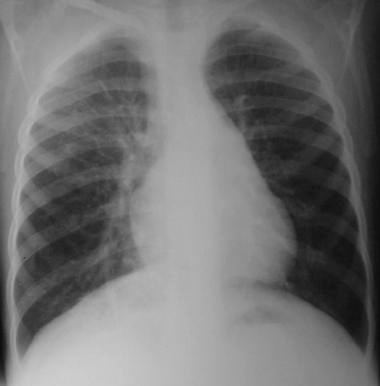

Radiología del tórax

• Rx. tórax PA: Observamos lesiones quísticas múltiples en base pulmonar derecho, aumento del volumen pulmonar a predominio basal derecho con mayor transparencia y discreta desviación contra lateral del mediastino.

• Rx. tórax lateral: Se aprecia mayor transparencia pulmonar y lesiones quísticas múltiples en todos los segmentos correspondientes al lóbulo pulmonar inferior derecho.

• No se observan lesiones de atelectasia, nódulos pulmonares ni adenopatias del mediastino